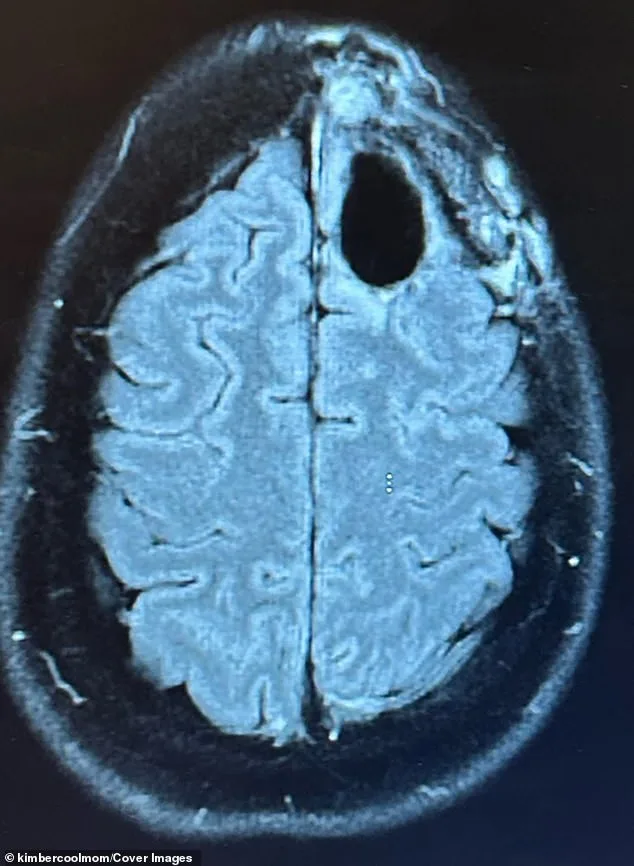

Kimberly Pelling's journey with grade-four IDH-mutant anaplastic astrocytoma, an aggressive and typically incurable brain cancer, began in August 2022. At 42 and four months postpartum, the mother of two young sons was thrust into a medical crisis when sudden seizures and persistent brain fog led to an emergency MRI. The scan revealed a lime-sized tumor in her frontal lobe, a region critical for cognitive function and emotional regulation. A biopsy confirmed the diagnosis: a tumor that typically leaves patients with a median survival of around 31 months. For Pelling, the revelation felt like a cliff edge — her life, and her family's future, hanging in the balance.

The standard protocol for such tumors involves aggressive treatment, including surgery, radiation, and chemotherapy. Pelling underwent this regimen, enduring months of grueling therapy that left her bedbound, battling fatigue, hair loss, and cognitive fog. Initially, a clear scan offered hope, but eight months later, a new inoperable tumor emerged. Her prognosis was now reduced to a single year. At this crossroads, Pelling made a decision that defied medical expectations: she stopped treatment and pivoted toward a radical lifestyle overhaul.

By 2025, a routine brain scan revealed no evidence of cancer. The news was surreal for Pelling, who had walked into the appointment expecting the worst. Yet, she acknowledges the uncertainty of her condition — cancer may return, and her story is not a guarantee of survival. Her message, however, is clear: hope persists even in the face of grim prognoses. Pelling now prioritizes living fully, running, caring for her sons, and sharing her journey as a source of inspiration, not a medical directive.